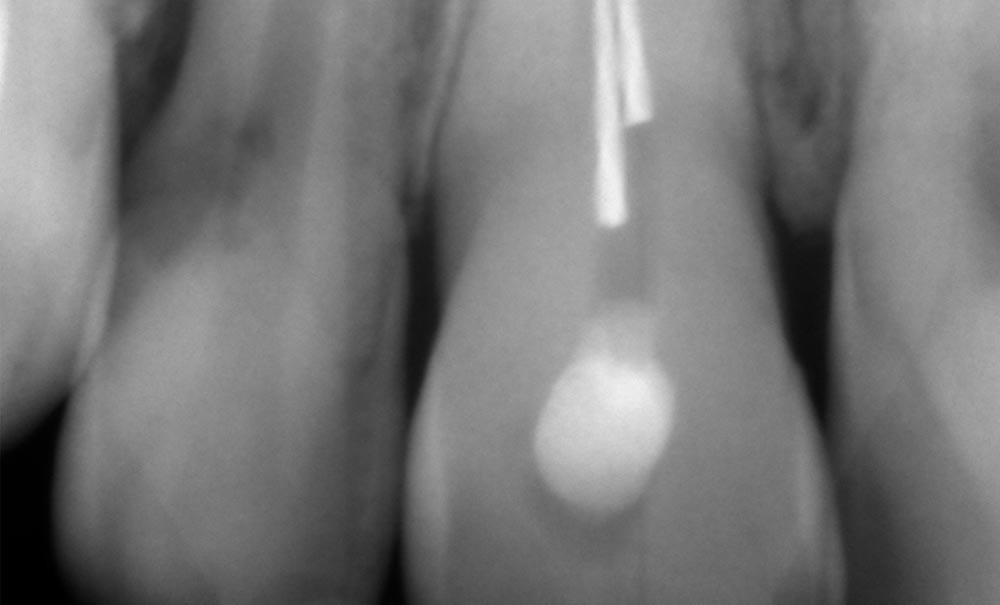

Parmi les reproches faits à ces systèmes de préparation canalaire, le risque de fracture est celui qui est le plus avancé. Et quelle frustration pour le praticien lorsqu’elle…